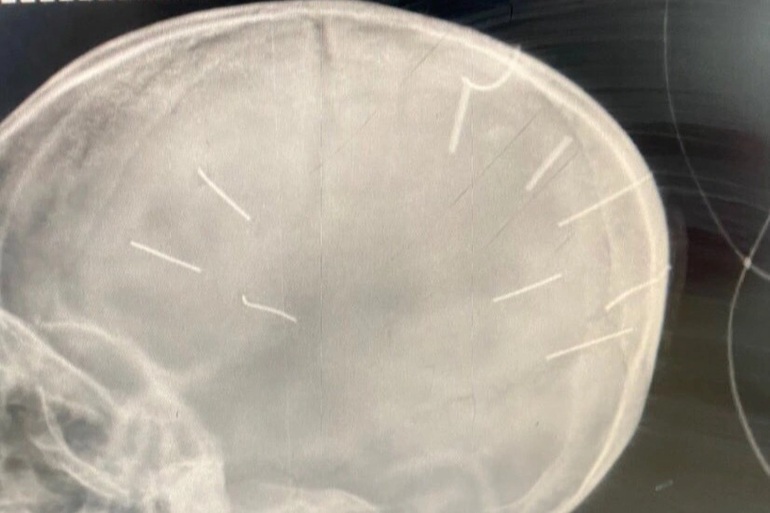

Và bây giờ tim tôi như thắt lại khi nghĩ đến bé gái mới ba tuổi với 9 cây đinh găm trong đầu. Tôi thật sự ước rằng tôi chưa đọc những chi tiết miêu tả hành động gã đàn ông đó làm với con. Mình dẫm phải một cái gai nhỏ cũng đau nhức mất ăn mất ngủ. Trời ơi, cháu bé đã chịu đựng nó khủng khiếp đến như thế nào?

Hình ảnh chụp X-quang của bé 3 tuổi bị 9 cây đinh ghim trong hộp sọ khiến cộng đồng xót xa (Ảnh: Bệnh viện cung cấp).